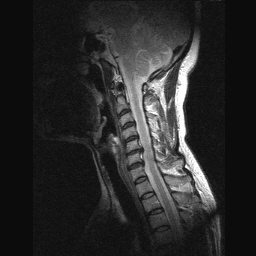

* ֹǰ (ֹȣ : e3b556460eae ) ǰ : 140ȣְ 140-190ȣ ο,ûҳ ɼ : 40~49 Ű 158 Cm ü 55 Kg μϼ ۷ հ 180,000 * (ID : hyangme902) ó Tel: 031-841-**** H.P: 011-717-**** E-mail hyangme902@naver.com : ν **2 ****Ʈ3902ȣ Ž ũ Ѵ MRI ˾Ұ, ô 15 Կ , ڿ Ƴ, Űʾ Ͽ, **ѹ溴 ġ 10 ƽϴ. ȸ ȣҳԴϴ. , ü Ư Ű 158 Cm ü 55 Kg 45 ȯ 1C.ٺҸ, 6C.ڸ , 6C. κ Ḳ , 6C.ھ Ḳ , 6C.ڻ , 7C. , 7C.Ȳġ, 1T.ڼհ ü ̳ , 1T.Ȳġ, 1T. κ , 1L., 3L.ڽѻ Ǵ Ҽ, 4L.ڿ, õ().ھ , |